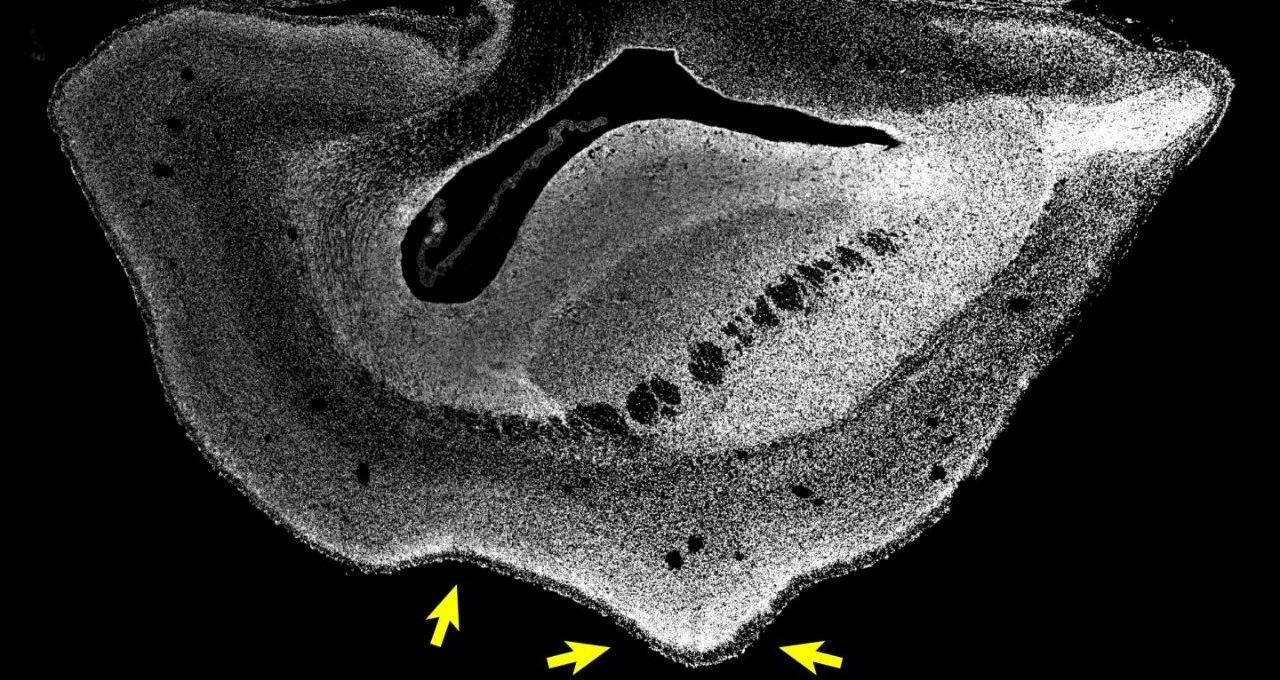

101日龄普通狨猴胎儿的大脑切片 图片来源:HEIDE ET AL. / MPI-CBG

ARHGAP11B是一种人类特有的基因,过去的研究认为它可能与大脑发育有关。近日,在《科学》发表的一项研究中,研究人员将ARHGAP11B基因转入普通狨猴胚胎内。结果显示,101日龄(正常出生时间前50天)的普通狨猴胎儿大脑的新皮质变大,且大脑表面折叠增加,其皮质板也发育得更厚。此外,研究还发现,一些在灵长类演化过程中数量增加的神经元类型,在这种转基因胎儿的大脑内也有所增加。这一研究证明,人类特有的基因ARHGAP11B的充分表达,会导致灵长类大脑变大,从而说明这一基因在人类大脑的演化过程中,起到了重要的作用。